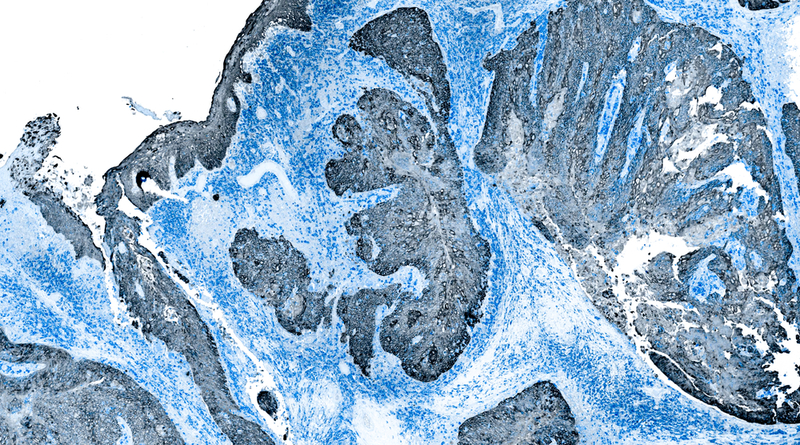

A chimeric antigen receptor (CAR) T-cell therapy that targets the protein mesothelin showed no evidence of major toxicity and had antitumor activity in patients with malignant pleural disease from mesothelioma, according to results from a phase I clinical trial presented at the AACR Annual Meeting 2019, March 29–April 3.

The investigators recruited 21 patients with malignant pleural disease (19 with malignant pleural mesothelioma, one with metastatic lung cancer, and one with metastatic breast cancer); 40 percent of them had received three or more lines of prior therapy. After cyclophosphamide preconditioning, IcasM28z CAR T cells were injected directly into the pleural cavity using an interventional radiology procedure.

The investigators evaluated multiple clinical, radiological, and laboratory parameters in the patients who received the CAR T cells and found no evidence of toxicity at the doses tested. CAR T cells were found to be persistent in the peripheral blood of 13 patients during the 38-week evaluation, and their presence was associated with more than 50 percent decrease in the levels of a mesothelin-related peptide in the blood and evidence of tumor regression on imaging studies.